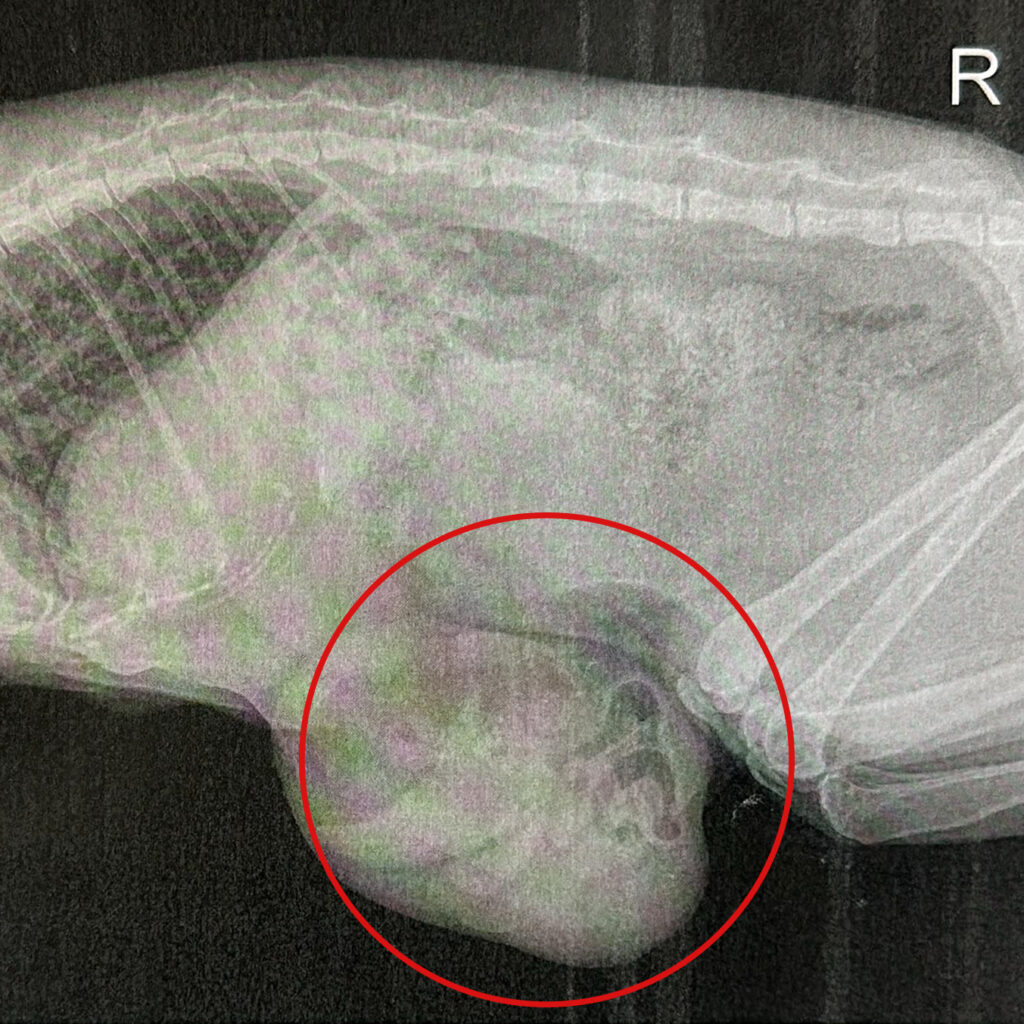

Als wir Hedwig vorsichtig aus der Box nahmen, stockte uns der Atem. An ihrem Bauch wölbte sich eine faustdicke, pralle Beule nach außen. Die Stelle war hart, extrem schmerzhaft und bei jeder Berührung maunzte Hedwig klagend.

Hedwig ist in Lebensgefahr – dieser Bauchdeckenbruch musste sofort operiert werden.

Hedwigs Bruchpforte war vermutlich durch frühere Geburten vorhanden, so kam es bei der jetzigen Schwangerschaft zum großen Bruch. Darmschlingen hatten sich durch den Bruch nach außen gedrückt und verdreht.

Wenn Darmgewebe eingeklemmt wird, kann das innerhalb kürzester Zeit tödlich enden. Der Blutabfluss wird gestört und der Darm könnte absterben.

In der Not-OP wurden die Darmschlingen vorsichtig in den Bauchraum zurückverlegt und der Bruch der Bauchdecke sorgfältig vernäht. Einige Tage musste Hedwig in der Tierklinik verbringen, bis sie wieder bei Kräften war. In der Zeit war nicht sicher, ob sie das alles überleben würde. Und die lange Zeit in der Klinik hat ein großes Loch in unsere Tierheimkasse gefressen … Mehr als 1800 Euro mussten wir allein für ihre Not-OP aufbringen. Noch dazu kommen Medikamente, Pflege und die Nachsorge.